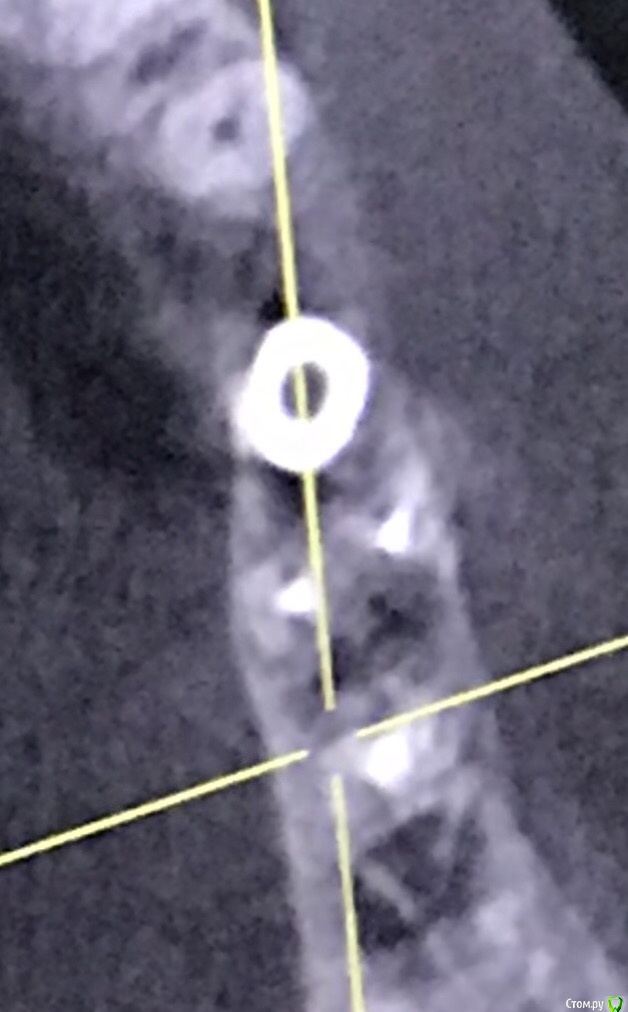

111 Опубликовано 26 декабря, 2020 Автор Поделиться Опубликовано 26 декабря, 2020 (изменено) Iroil, спасибо большое за ответ.46 был кариес но не болел, периодонтита не было, никаких воспалений на верхушках не было. То есть 46 просто пролечили - обработали каналы, заложили кальций, и тд. Делалось под микроскопом, доктор очень хороший. По поводу 45 - изначально кости было достаточно по высоте, по объему пришлось подсыпать gen-oss 0,5 в момент имплантации, плюс сст с бугра. Вообще всё было хорошо, особо сильно не болело, без отёка зажило. В момент снятия швов - обнаружилась убыль кости в области 46, слегка оголился корень ближайший к 45, но мы как-то это не обсуждали с доктором. Установили Фдм, все ок.И вот пришло время ортопедии - это было летом 2019 - ортопед не захотел работать с имплантом, у которого на снимке оголена шейка. Десны достаточно при этом. Имплант не запротезирован.Спустя пару дней на визите у хирурга - я прошу выкрутить 45, мне отказывают, принято решение либо оставить как есть, либо подсыпать кости немного.Сейчас, декабрь 2020, я хожу с фдм и уже точно понимаю, что надо переустановить 45, но хирург предлагает 2 варианта:- оставить как есть и делать ортопедию (т.к. десна хорошая);- удалить 45 и 46 для создания удобного рабочего поля и имплантация 45, 46.Вот я пытаюсь понять, нельзя ли просто 45 выкрутить? Аккуратно удалить 45 не получится? (Очень не хочется расставаться с 46, сам по себе он не болит при накусывании и постукивании). Изменено 26 декабря, 2020 пользователем 111 Ссылка на комментарий